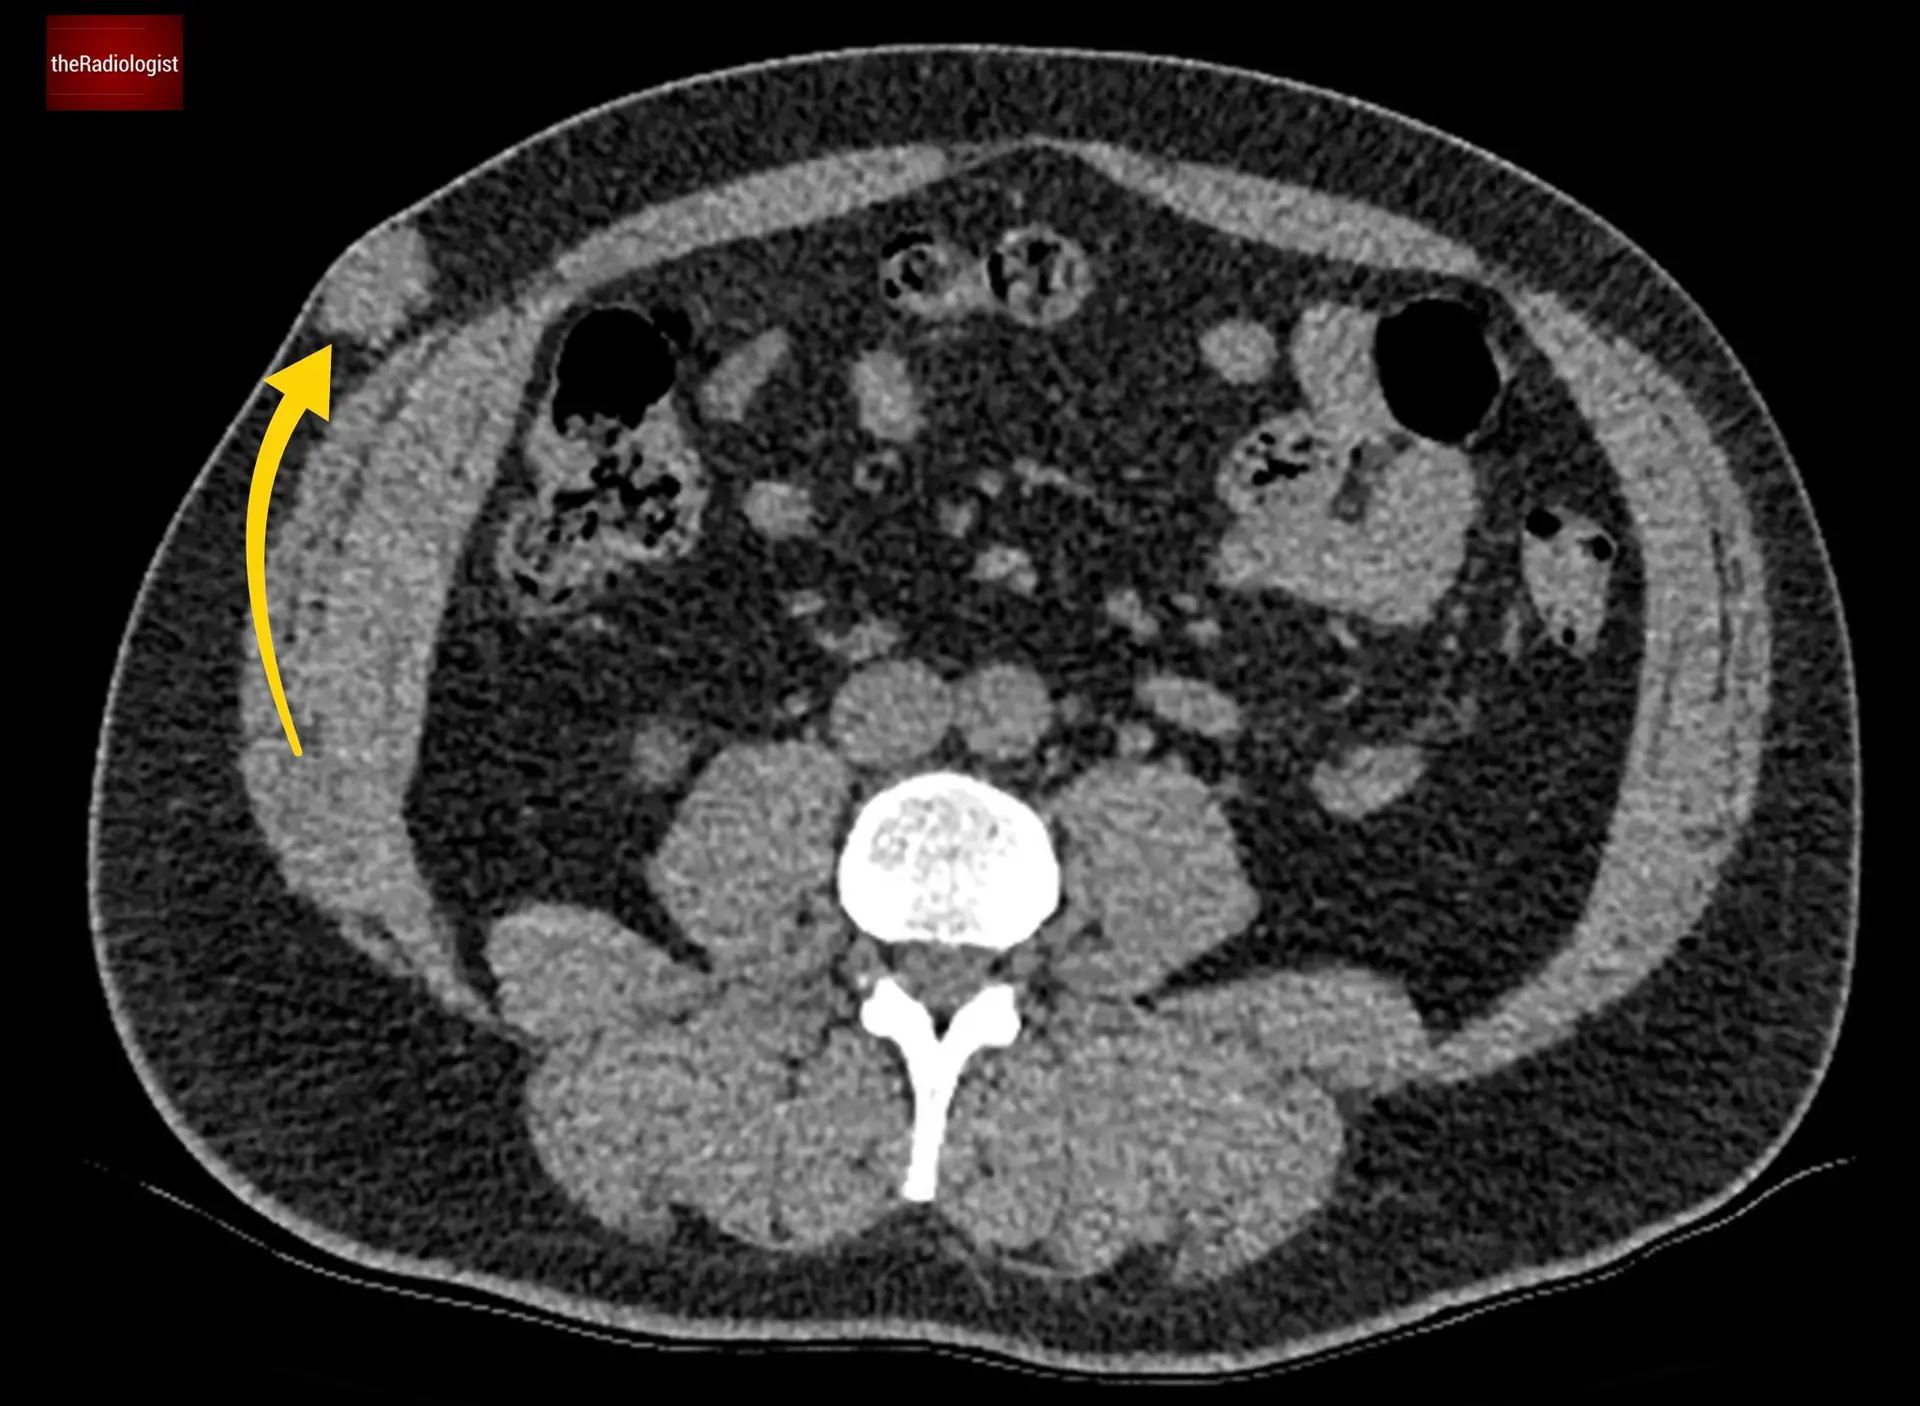

Assessing the right iliac fossa

When you suspect a right iliac fossa (RIF) abnormality, first start by identifying the caecum. I do this by tracing the colon all the way from the rectum back to the origin. Once you find this, in normal circumstances you will find two things communicating with it. Firstly the terminal ileum and then the appendix.

You should be able to recognise the terminal ileum as communicating with the rest of the small bowel but also look out for some fat density which you will normally find with a normal ileocaecal valve as we can see below.

Separate to the terminal ileum we can see a second structure communicating with the caecum – this is a dilated appendix.

When we follow the appendix in this case we can see it is enlarged with surrounding fat stranding – this is acute appendicitis. It can sometimes be difficult on CT to make the call. I usually use the diameter of the appendix and the presence of surrounding fat stranding to help me make the call. A high density appendicolith within the appendix also adds weight to the diagnosis.